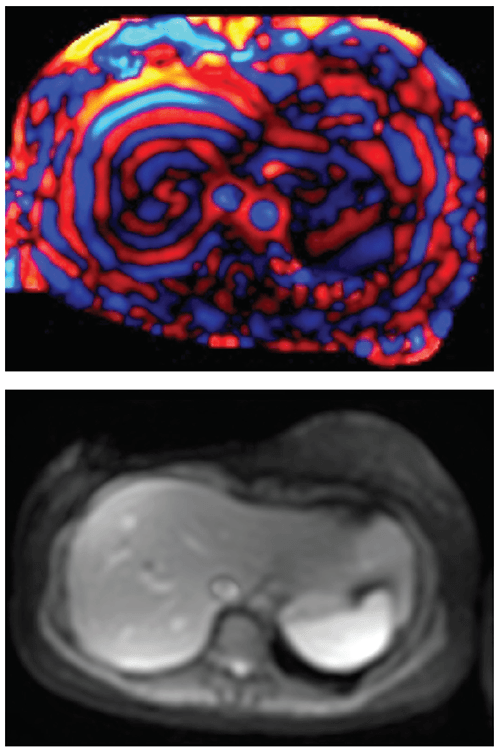

Non-invasive magnetic resonance elastography (MRE) can be used reliably to measure liver stiffness, according to a study led by experts at Cincinnati Children’s.

This relatively new technique offers a way to detect early signs of chronic liver disease while relying less upon surgical liver biopsies and their inherent risks.

Trout and colleagues studied the reliability of MRE with the consent of 24 adult volunteers. The project involved four MR imaging systems from two manufacturers evaluated across various field strengths and pulse sequences. The team found the technique to be both reliable and repeatable.